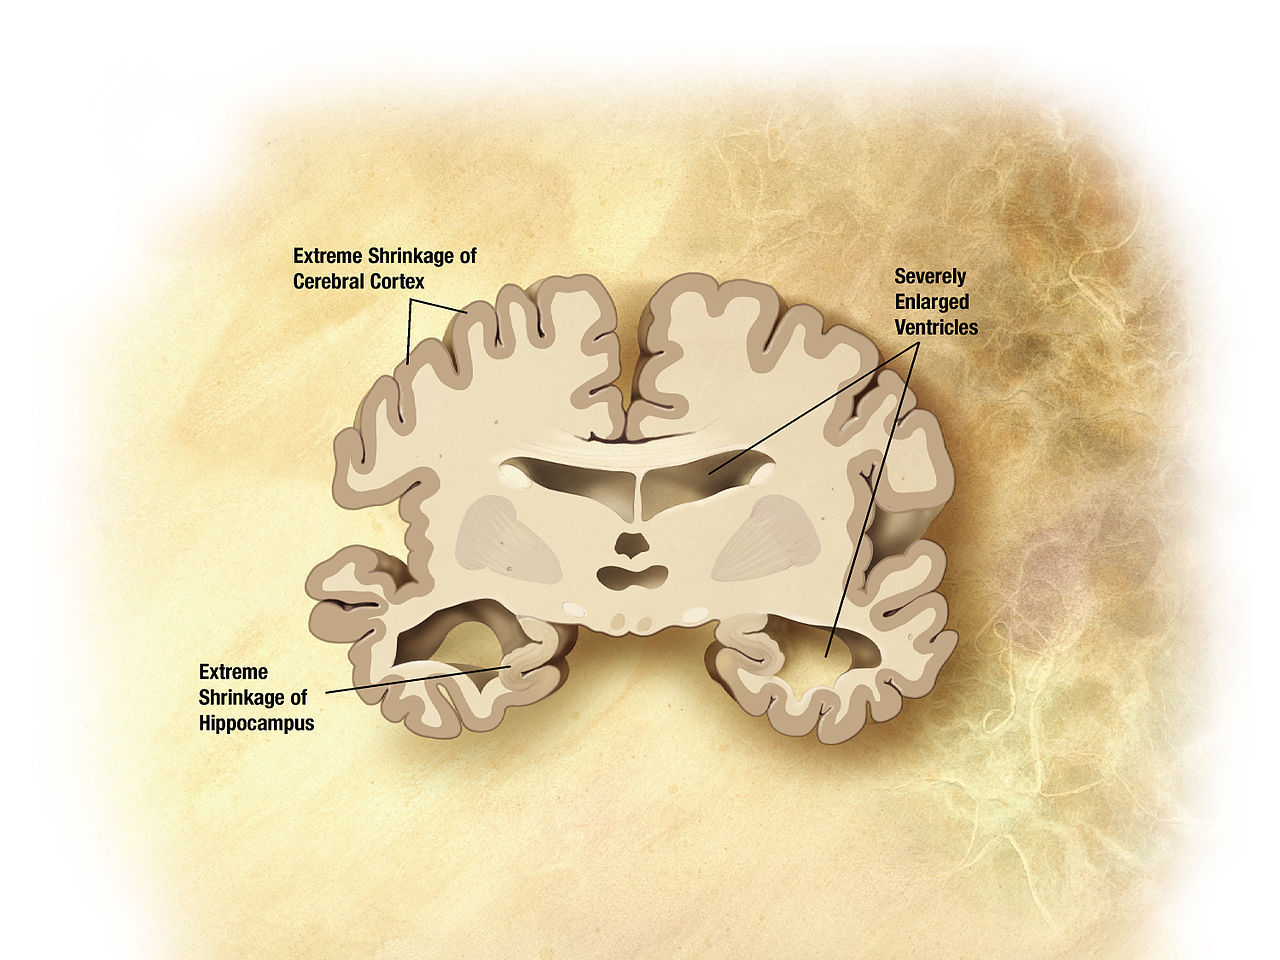

IBM utvecklar AI som kan upptäcka Alzheimer Årtionden innan sjukdomen bryter ut IBM utvecklar AI som kan upptäcka Alzheimer Diagram på en hjärna med Alzheimer Foto: Wikimedia Commons Forskare på IBM har utvecklar en artificiell intelligens som ska kunna upptäcka risken för att en person drabbas av Alzheimers sjukdom flera årtionden innan sjukdomen eventuellt bryter ut. Tekniskt sett så kan man redan idag upptäcka det genom att analysera en persons ryggmärgsvätska och leta efter peptiden amyloid-beta. Detta är dock en procedur som är mycket omständlig, dyr, tidskrävande samt rätt otrevlig att bli utsatt för. IBM:s AI mäter istället förekomsten av amyloid-beta genom ett vanligt blodprov där man identifierar proteiner som ska kunna visa hur hög förekomst av amyloid-beta det finns i patientens ryggmärgsvätska. IBM skriver själva:

Att upptäcka Alzheimer på ett tidigt stadium är dels viktigt för att sätta in åtgärder för att hindra sjukdomen från att bryta ut, dels för att forskare ska kunna studera patientens hjärna innan den blir för hårt åtgången av sjukdomen. En av anledningarna till att det inte finns något botemedel mot Alzheimers sjukdom uppges vara att man inte har kunnat studera Alzheimers-patienters hjärnor innan sjukdomen brutit ut på allvar.